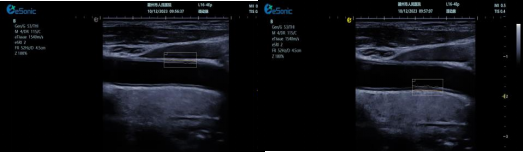

3377体育超声系统融合 e 智 IMT 内中膜自动测量、超高频高分辨线阵探头、TCCD、心脏彩色多普勒超声等高端台式彩超功能,数据处理能力强,大幅提升人体组织显示分辨率。优势体现为:

? e 智 IMT 内中膜自动测量可自动检测厚度,智能匹配与包络,自动设置取样框,实时或冻结状态下均可测量前壁及后壁厚度,提供多组数值,减少人工误差,便捷准确。

超高频探头能清晰显示颈动脉内中膜及斑块细节,辅助判断斑块易损性。